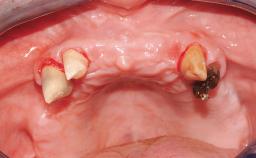

Rehabilitating an Edentulous Maxilla with a Fixed Dental Prosthesis Following Provisional Immediate Loading

This case features the flapless computer-guided placement of 7 bone-level implants, distributed to provide maximal support for the prosthetic framework. A rigid one-piece metallic framework was utilized as an interim restoration to reduce the risk of fracture associated with this prosthetic design. As part of the clinical examination, the SAC Assessment Tool was used, resulting in a surgical and restorative risk classification as “complex”.

Case Type Edentulous Maxilla

# of Implants 7

Guided Surgery Yes

Prosthesis Type FDP